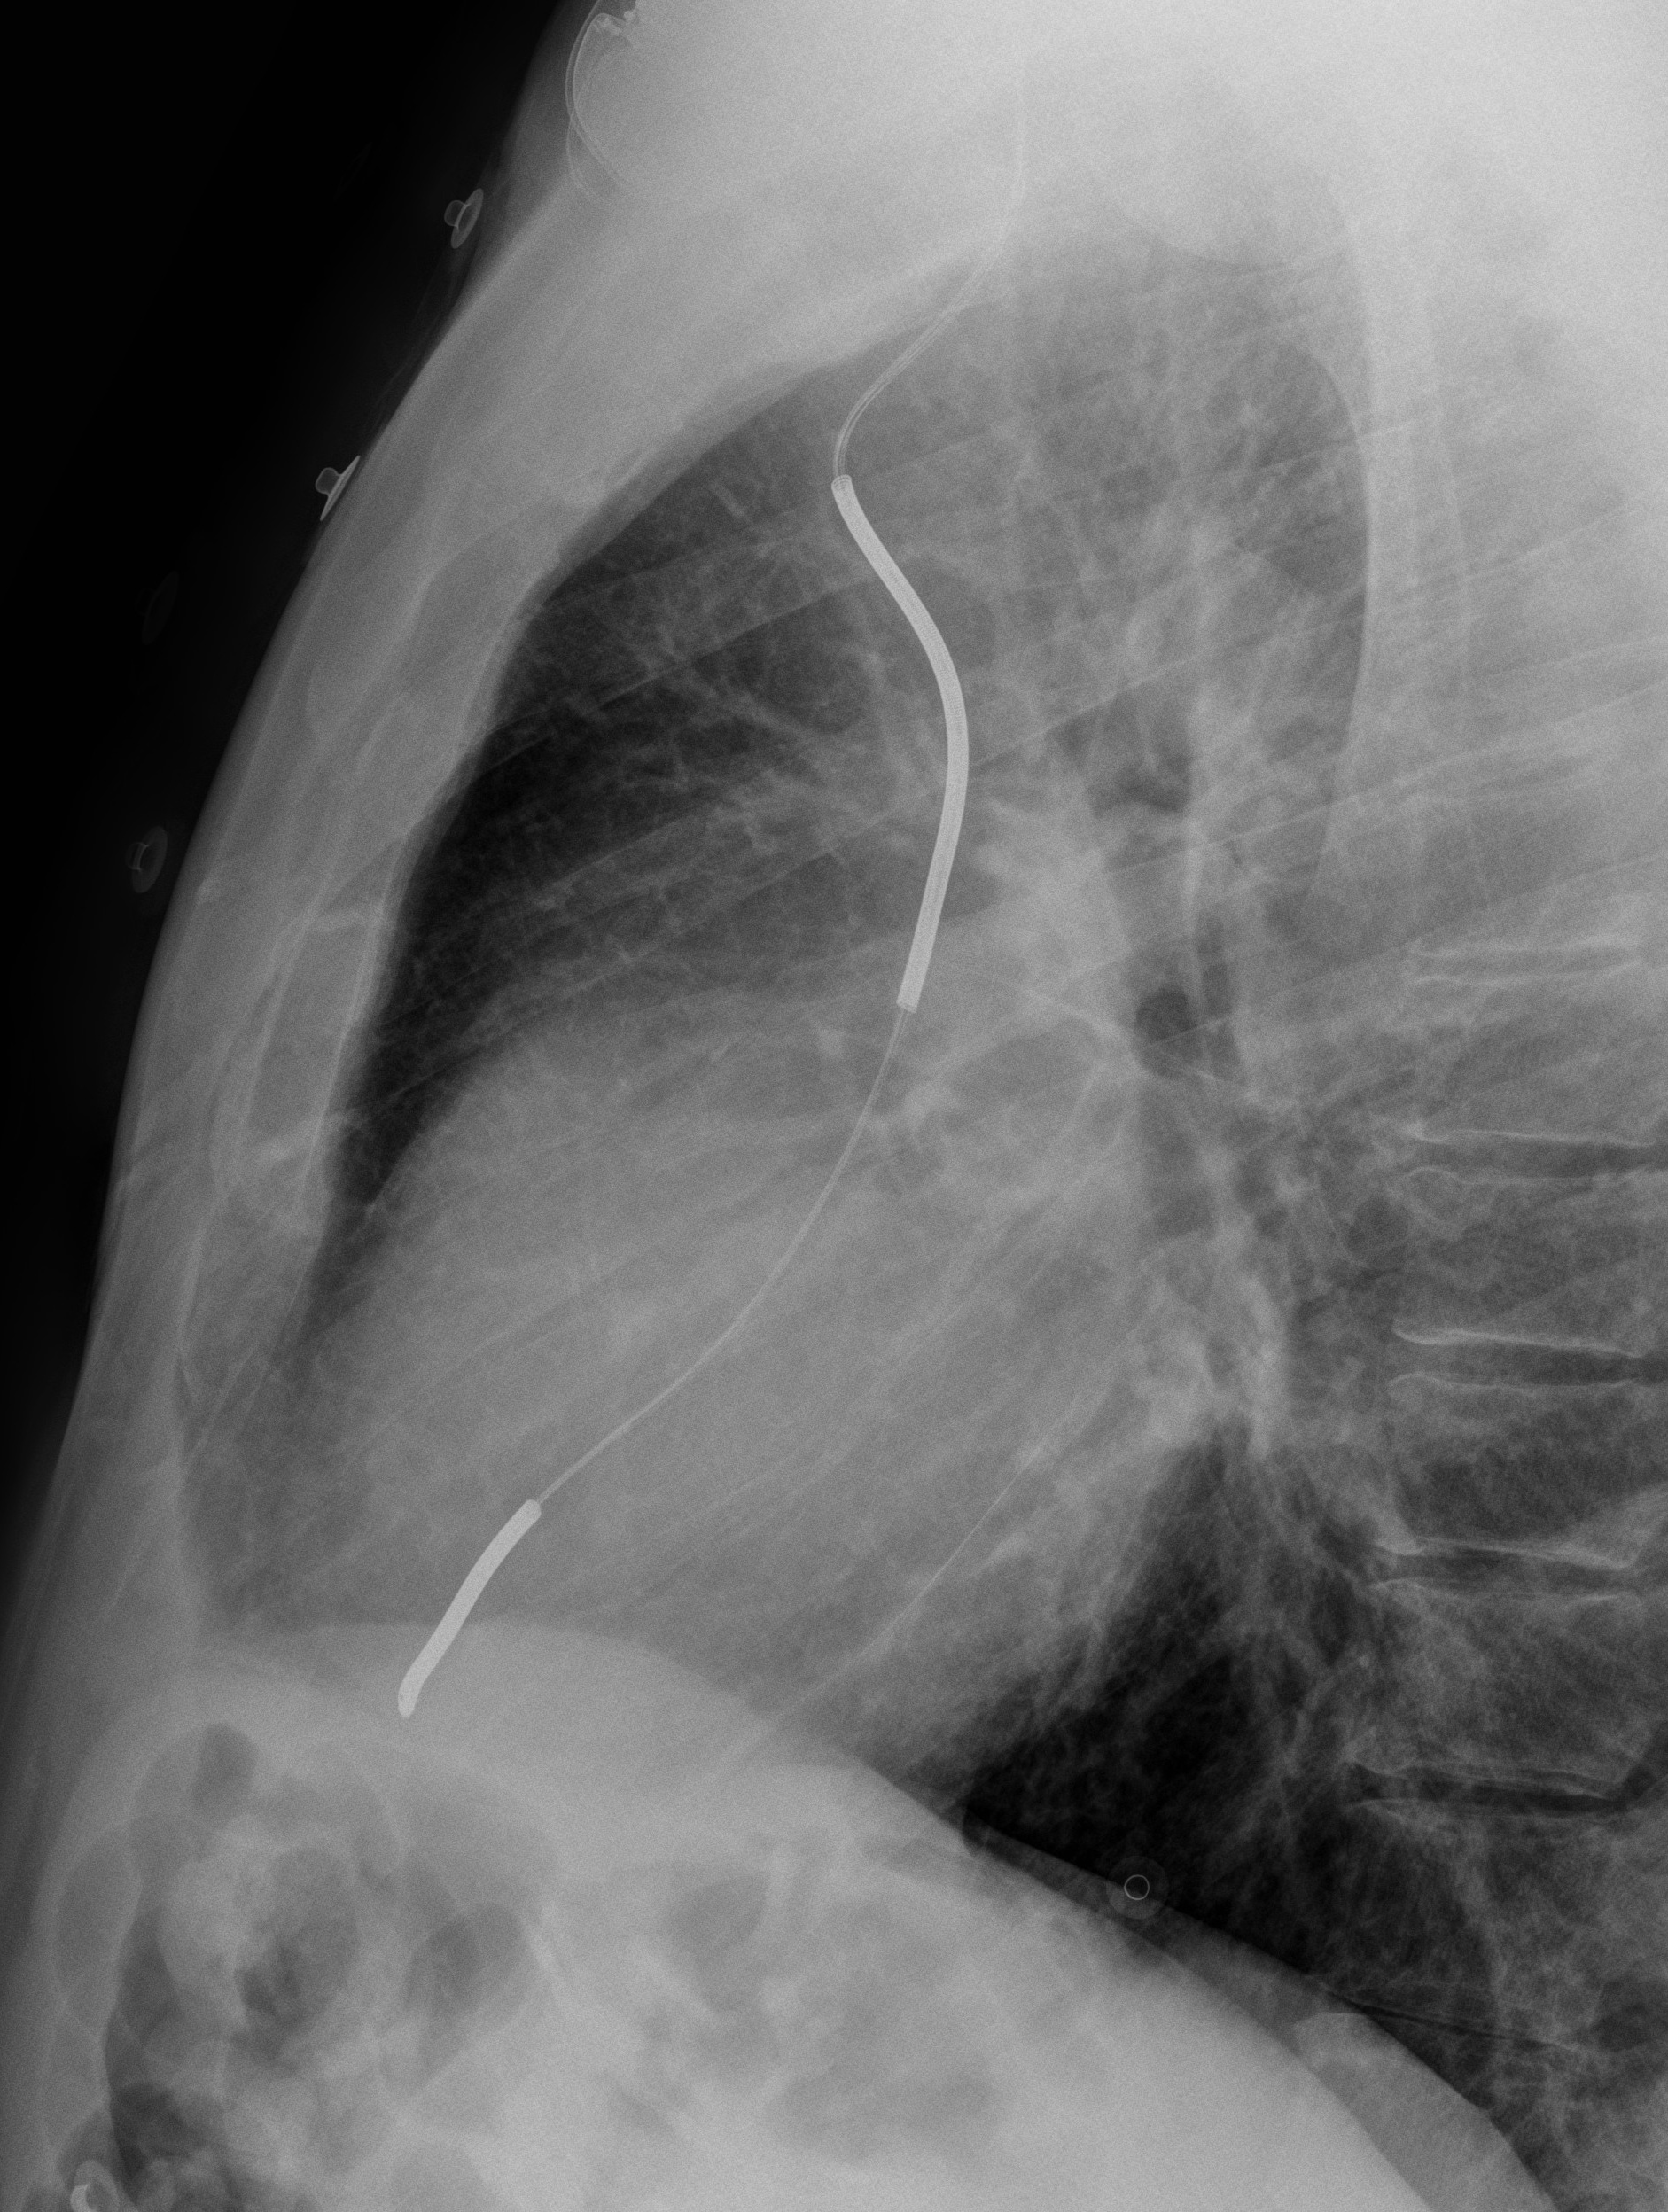

Gallery Cardiac Other ICD Lat

ICD Lat